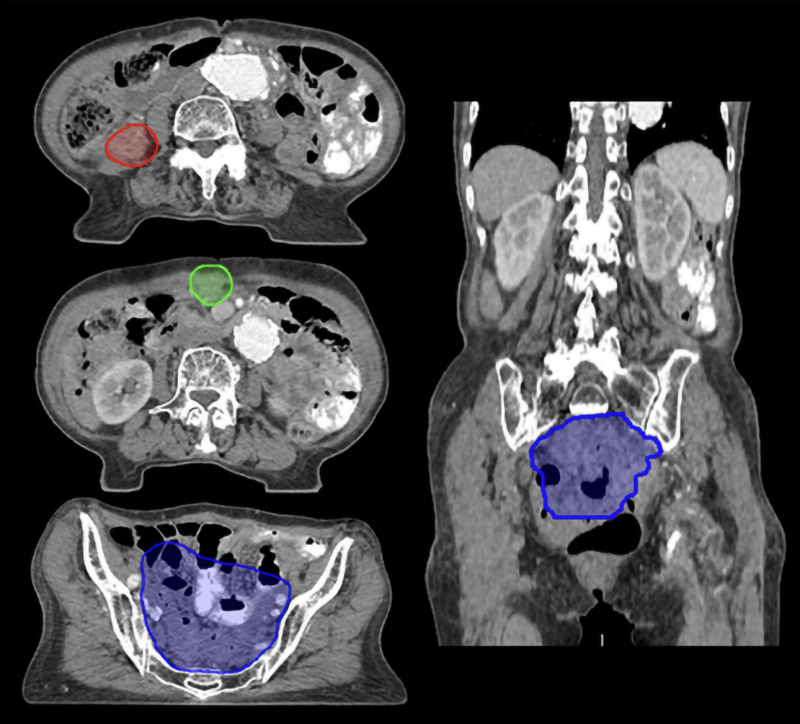

Background: Recurrent ovarian cancer is often treated with chemotherapy, but many patients experience multiple recurrences with progressively shorter intervals and poorer prognosis. Repeated chemotherapy reduces patients' quality of life. Stereotactic Ablative Radiation Therapy for Recurrent Ovarian Cancer (SABR-ROC) (KGOG3064/KROG 2204) is an ongoing trial investigating the clinical efficacy of stereotactic ablative radiation therapy (SABR) for recurrent ovarian cancer. This study aimed to assess treatment planning consistency and protocol adherence in a prospective, randomized, multicenter phase III trial.Methods: In this dummy run study of a prospective, randomized, multicenter phase III trial (SABR-ROC), we examined the variability in target delineation, dose prescription, and treatment planning among 10 centers participating in the SABR-ROC trial. Four representative cases, each presenting with different anatomical sites and treatment challenges, were selected for evaluation. Target volume consistency was measured using the Dice similarity coefficient, and treatment plans were reviewed to follow predefined goals and constraints in the protocol.

Results: Overall agreement in target delineation was low, with mean Dice similarity coefficients of 0.278 and 0.255 for gross tumor volume and planning target volume, respectively. Consistency was higher for cases involving lymph node and lung metastases but significantly lower for intraperitoneal and liver seeding metastases due to challenges in target delineation. Treatment plans generally adhered to protocol dose prescriptions, with minor deviations in planning target volume coverage, particularly in cases with multiple small metastases. Deviations from organ-at-risk constraints frequently occurred in cases involving small bowel proximity.